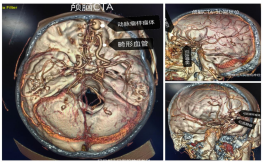

5月22日,阿坝州人民医院神经外科成功为一名57岁患者实施医院首例复杂颅脑硬脑膜动静脉瘘(DAVF)开颅夹闭手术。这场跨越高原医疗技术壁垒的“生命保卫战”,不仅填补了医院在该领域的空白,更标志着川甘青结合部复杂脑血管疾病救治能力实现重大突破。

本区域诊断破局。团队突破高原设备限制,通过增强MRI+CTA影像与华西医院专家远程会诊,锁定隐藏在“头痛”背后的罕见病因,打破“高原头痛=缺氧/高血压”的固有认知;开颅夹闭“零误差”。在缺乏介入治疗条件的情况下,团队创新采用术中超声实时定位技术,在前颅底矢状窦旁精准夹闭瘘口,完整保留正常血管结构,实现“零并发症”治愈;多学科协作模式。神经外科联合影像科、麻醉科建立“黄金会诊链”,从接诊到确诊仅用6小时,开创高原地区复杂脑血管病多学科联动新模式。

2.CT与MRI:对良性DAVF敏感性较低;对侵袭性DAVF,可显示异常血管,颅内出血,局部占位效应,脑水肿,脑积水,静脉窦血栓形成及颅骨骨质异常等征象。

3.CTA与MRA:可显示异常增粗的供血动脉和扩张的引流静脉及静脉窦,对瘘口位置及“危险吻合”显示欠佳。